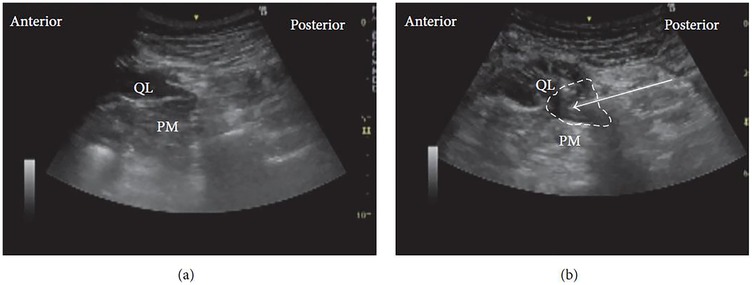

For the procedure, the patient is typically positioned supine. A high-frequency linear ultrasound probe is applied over the Petit triangle until the QL muscle is clearly visualized (Figure 3a). The needle is advanced toward the anterolateral surface of the QL at the junction with the transversalis fascia, and local anesthetic is injected at this site. Proper placement of the injectate beneath the transversus abdominis aponeurosis is confirmed using real-time ultrasound visualization (Figure 3b).

Ultrasound images display anatomical layers from anterior to posterior. Panel (a) shows labeled muscle layers: external oblique (EO), internal oblique (IO), transversus abdominis (TA), and quadratus lumborum (QL). Panel (b) highlights a specific area in the QL muscle, outlined with a dashed line and indicated by an arrow, retaining the same muscle labels.

Figure 3. Ultrasound images of lateral QLB: (a) before injection and (b) after injection. EO, external oblique; IO, internal oblique; TA, transversus abdominis; QL, quadratus lumborum. White arrow: needle trajectory; white dotted line: spread of local anesthetic [Reproduced from Ueshima et al. (28). © John Wiley & Sons, Inc. Distributed under the Creative Commons Attribution License, CC BY 4.0].